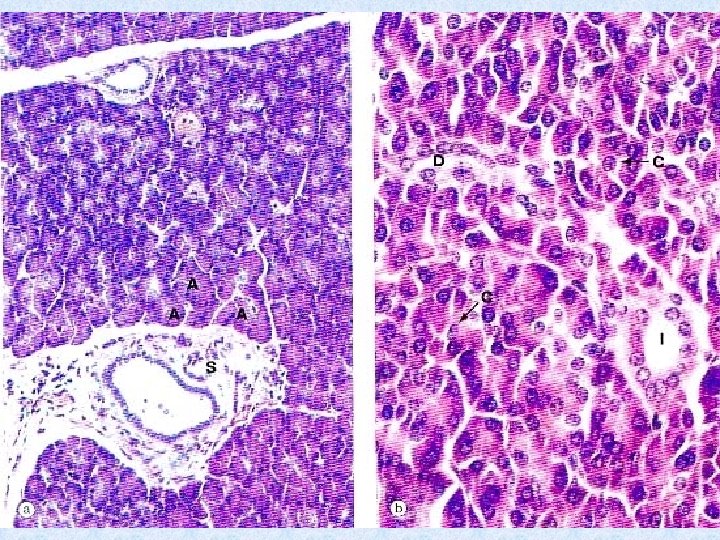

Pancreas Has exocrine and endocrine components Under the influence of autonomic nerves, gastrin and CCK Secretes enzymes that digest proteins, lipids and carbohydrates Secretes insulin, glucagon, somatostatin, and some other hormones Cells - Insulin Cells - Glucagon Cells - Somatostatin

Pancreatic acini Pyramidal shaped cells Lumen Intercalated ducts